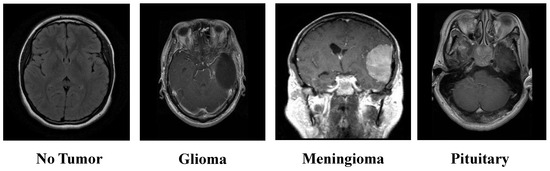

The Kaggle-sourced brain tumor MRI dataset represents an extensive resource, encompassing 7023 MRI scans. These images are classified into one of four categories: Glioma tumors, Meningioma tumors, Pituitary tumors, and images where no tumor is present [26]. This classification structure is visually depicted in Figure 2, offering a clear overview of the dataset’s composition. The dataset integrates images from Figshare, the SARTAJ, and the Br35H datasets, ensuring a robust variety of MRI scans. The dataset is partitioned into training and testing subsets. The training set comprises 1457 Pituitary, 1339 Meningioma, 1321 Glioma, and 1595 No-tumor images. Meanwhile, the testing set includes 300 Pituitary, 306 Meningioma, 300 Glioma, and 405 No-tumor images.

Figure 2.

Overview of the brain tumor MRI dataset.